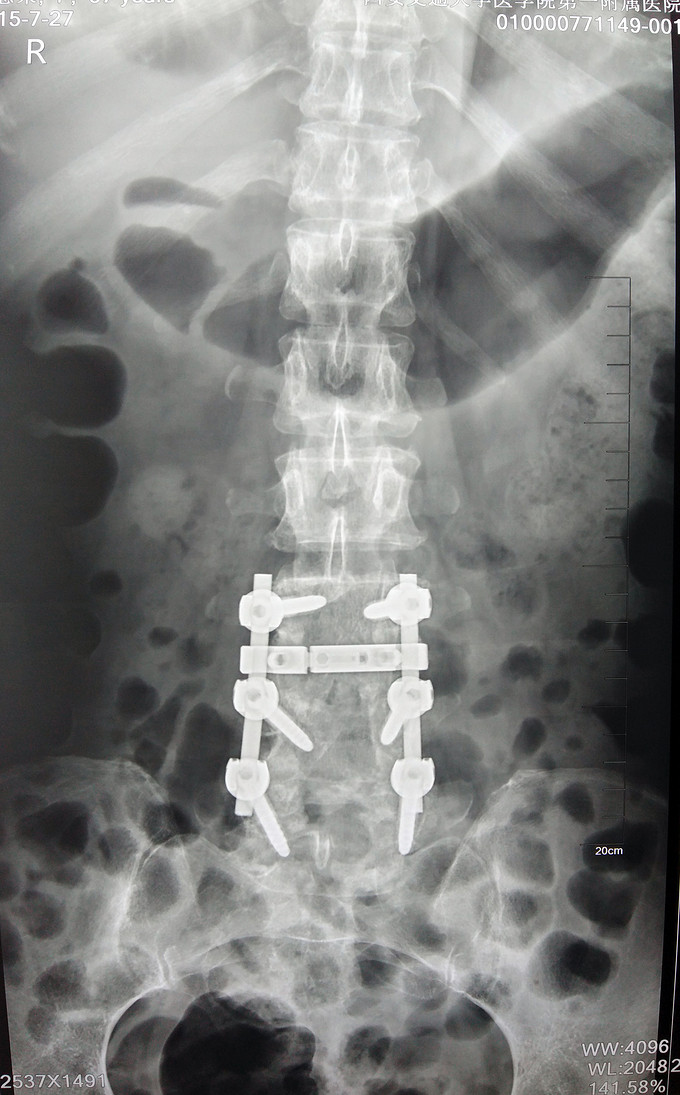

1.腰3-4结核 2.腰4-5椎管狭窄 因术前血沉比较高,所以予以HREZS抗痨治疗2周,血沉至44mm/h,患者一般情况较前好转。安排手术治疗:后路腰3-4椎间病灶清除椎板植骨+腰4-5减压植骨内固定融合术。

此患者腰椎结核伴有相邻节段椎管狭窄,所以兼有两者的症状。对于此病例我们考虑因患者椎体前方脓肿不明显,所以考虑一起行后方椎间隙病灶清除,植入自体椎板骨融合内固定,同时进行腰4-5后路减压内固定融合术。 不知大家对结核的病人一般是通过何种方式进行病灶清除的?选择原则是什么?